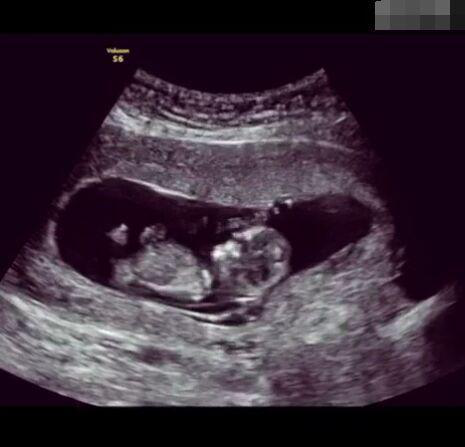

那些做了B超檢查確定胎兒男女,生下來(lái)后發(fā)現(xiàn)不對(duì)的,多半是因?yàn)樵贐超檢查時(shí)寶寶太調(diào)皮,以致影響了檢查準(zhǔn)確性。就比如說(shuō),有的女寶寶在媽媽肚子里玩自己的臍帶,把臍帶夾到了兩腿中間,B超就有一定幾率拍出來(lái)好像是男寶寶的特征,導(dǎo)致被誤認(rèn)為是男孩子。還有些男寶寶過(guò)分害羞,在做B超時(shí)雙腿緊緊并攏,醫(yī)生也很難判斷男女,只好大致猜測(cè)是女孩,就又造成了誤會(huì)。因此,B超亦不是萬(wàn)能的。